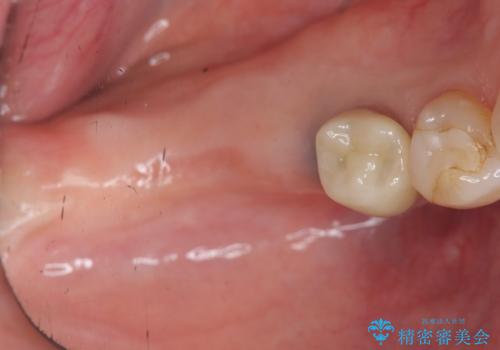

- 「数年前に入れたブリッジがぐらぐらする、診て欲しい。」と来院されました。

ブリッジを支える歯が割れてしまい、抜歯が必要であることと、骨の大きな吸収が見られました。